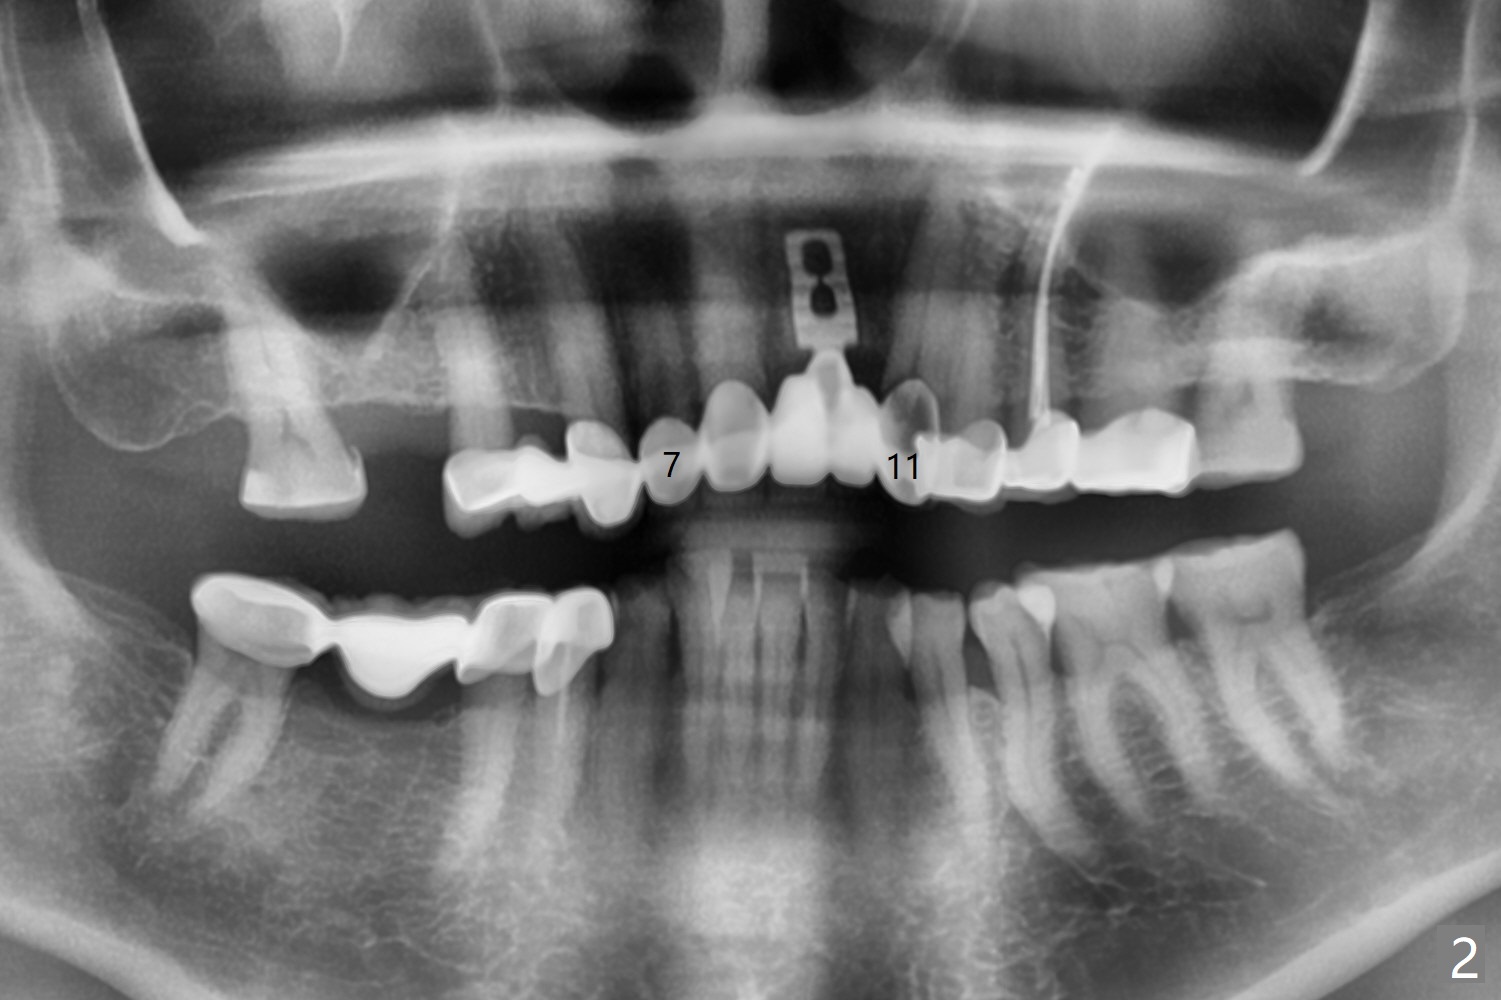

今天来一位57岁女,“前牙桥快掉了” (图一:7-11,桥在尖牙(11)端松动明显),不明白为什么左上中,侧切牙唇侧带有托牙树脂(*),影响局部卫生(^)。全景片(图二),CT(图三)显示刀柄植体,好像没有骨质吸收,但是修复体与基台脱离,树脂大概有美观作用。尖牙根尖瘘道(图一:>),阴影(图三 (B:颊侧),四)表明牙齿似乎无法保留,其余牙齿命运等待桥撤除后决定。琼脂取模,模型已制备,简易stent尚未完成。明天一早病人回来治疗,抽血一管制备骨块和PRF膜。